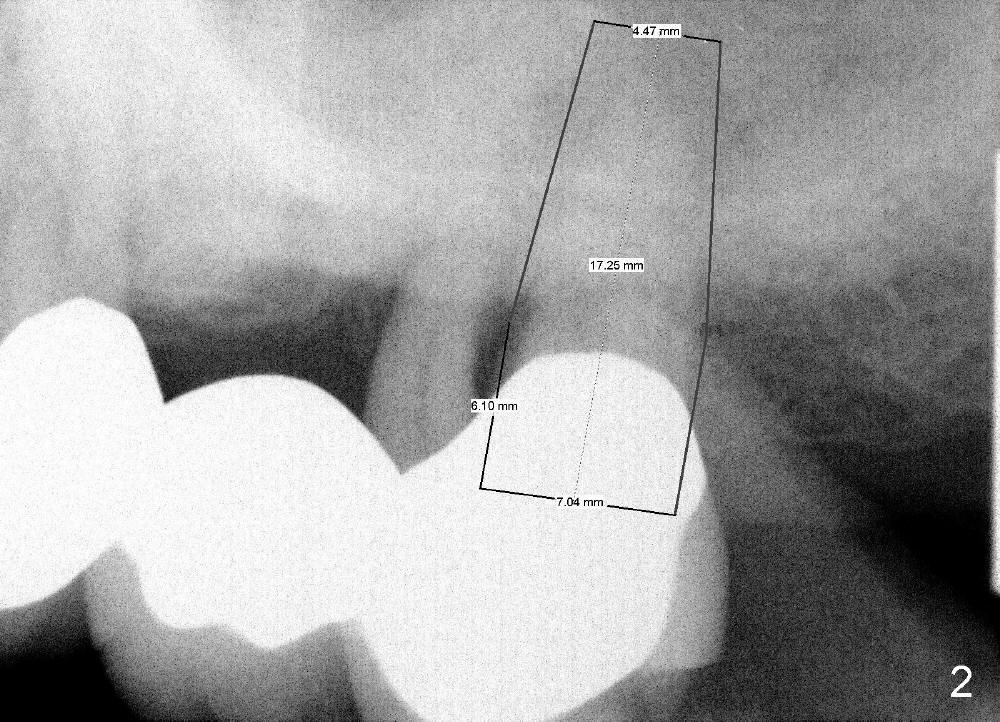

上周跟家人到Alaska玩,突然想起徐博需要植牙严重牙周病病例。当时知道今天也要为一位牙周病病人即可植牙(图一左上七号牙),随便写一片短文,想考考自己敢不敢在那里植牙,骨头高度有多少(是黑线还是红线)。今术前使用简易digital X-ray program,测量号牙骨头高度,十七毫米(图),是不是太大胆了?种植体部分捅进或者整个掉入上颌窦?能使用短些种植体吗?

分析上颌骨牙槽嵴高度有一定难度,主要是因为上颌窦,它的底板在这个病例特别白(图一:黑箭头(1)),好像这就是牙槽嵴高度,其实第一部分下面有骨质比较疏松部分(2),所以初步看:牙槽嵴高度至少1加2(黑箭头)。但是左上七牙根尤其是鄂侧根(P)不是空空地伸入上颌窦,它的根尖周围还有阴影,阴影上面可能还有骨皮质,所以能与种植体接触的骨头高度应该是图一两个红箭头总和,这就相当可观了。初步设计显示我们可以植入七乘十七毫米种植体(图二),其中三毫米(长度)与牙龈接触。